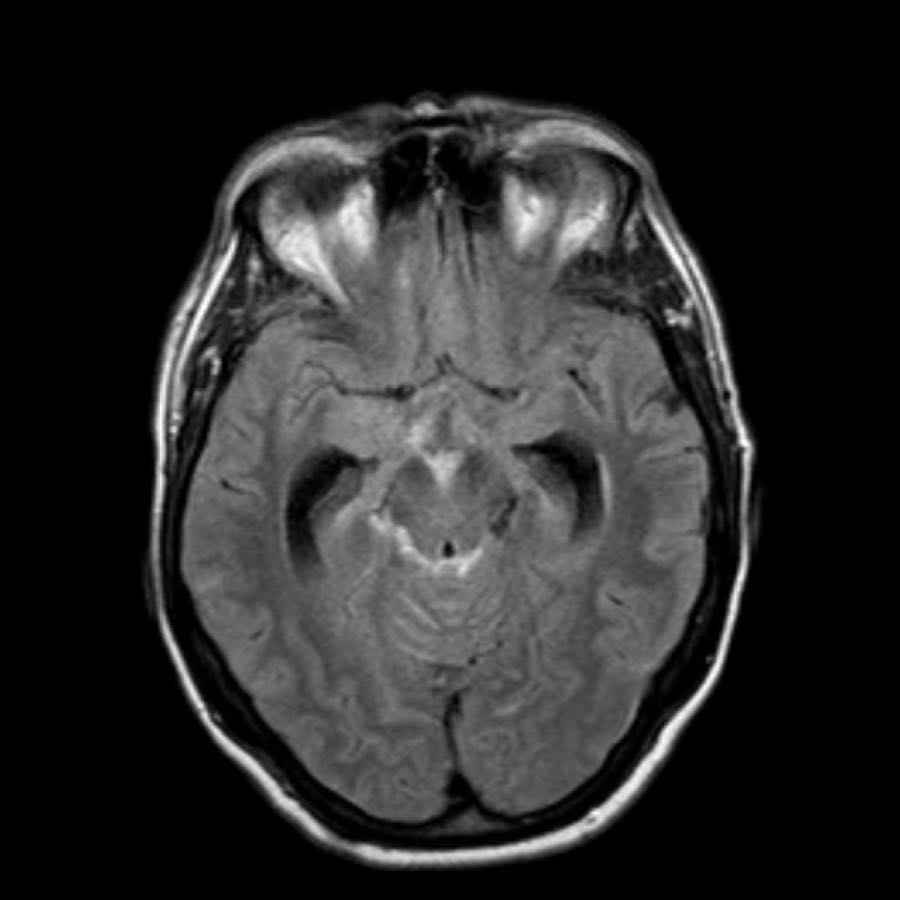

Bệnh nhân này nhập viện với xuất huyết tiểu não.

Các hình ảnh chuỗi xung gradient echo cho thấy nhiều vi xuất huyết.

Đây có thể là hậu quả của tăng huyết áp lâu năm do vị trí trung tâm của một số vi xuất huyết.